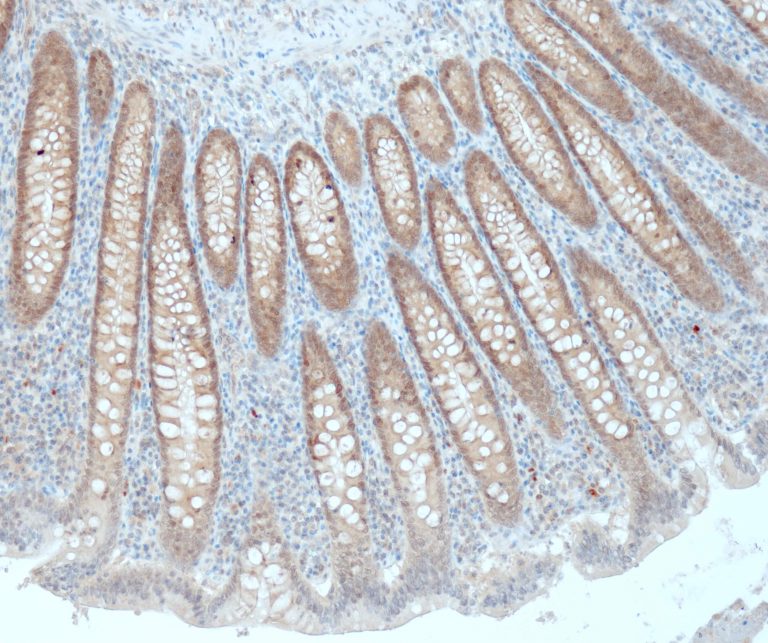

Gastrointestinal (GI) Pathology